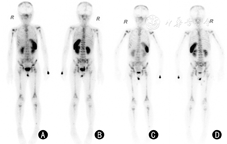

患者,女,7岁,因纳差1个月,间断四肢疼痛半个月伴后腹部肿块于2013年8月16日入院,入院后行剖腹探查术+左侧腹膜后肿瘤切取活检术,病理检查确诊为左侧腹膜后神经母细胞瘤(neuroblastoma, NB)Ⅳ期。患儿行化疗,化疗方案为异环磷酰胺+托泊替康+美司钠,第1~2次化疗;环磷酰胺+托泊替康,第3~4次化疗。经4次化疗后,超声示肿瘤体积稍缩小。于2013年12月26日行左侧腹膜后肿瘤切除术+左侧肾上腺切除术+胰头、脾门及肾门淋巴结清除术+左肾静脉修补术,术后病理示,符合NB化疗后改变,伴胰头、肾门及脾门淋巴结转移。术后继续化疗11次(化疗方案为环磷酰胺+托泊替康+美司钠,第1、7、10、11次化疗;环磷酰胺+长春新碱+顺铂+足叶乙甙,第2、3、6次化疗;异环磷酰胺+美司钠+托泊替康,第4次化疗;环磷酰胺+托泊替康,第5、8、9次化疗方案),患儿无发热、腹痛,于2014年12月出院。两年内患儿病情平稳,未行特殊治疗和检查。2016年12月15日,患儿行18F-脱氧葡萄糖(18F-fluorodeoxy glucose, 18F-FDG) 正电子发射计算机断层扫描(positron emission tomography/computed tomography, PET-CT),示双侧颈部、纵隔内及双侧腋窝、腹膜后、双侧腹股沟多发淋巴结肿大转移;右侧肾上腺团块状软组织密度影,FDG代谢增高,考虑转移;全身骨骼多处FDG代谢不均匀增高,考虑转移,再次入院。于2016年12月22日行右腹膜后肿瘤切除术+腹腔引流术+剖腹探查术。手术发现:(1)右侧腹膜后有2个大小约5 cm×5 cm×5 cm肿块,位于胃、肝、右肾之间,下腔静脉与右肾静脉分叉处上下各1个,包块内为实性结构,血供丰富,包膜基本完整,为肿瘤淋巴结转移表现;(2)探查肾周、腹主动脉旁、脾门和肠系膜淋巴结均无肿大。术后组织病理学示,左侧腹膜后淋巴结NB转移(分化差型,Shimada分型为uFH型),脉管内见瘤栓(图1)。待术后8周患儿病情平稳后,为进一步评估患儿治疗效果,分别行99mTc-奥曲肽显像(99mTechnetium-Hydrazinonicotinyl-Tyr 3-Octreotide, 99mTc-HTOC),见颅骨多处、双侧肩关节、双侧肱骨、双侧肋骨多处、脊柱多处(胸椎、腰椎、骶尾椎)、骨盆多处、双侧股骨和双侧胫骨奥曲肽高表达显影(图2),多发NB骨转移及全身骨显像(whole body bone scan, 99mTc-MDP),左侧股骨上段、右侧股骨下段片状放射性增高影,考虑转移性骨肿瘤。

本例患儿18F-FDG PET-CT显像不仅显示全身多处骨骼的转移,还显示全身多处软组织转移。因此,18F-FDG PET-CT对NB的临床分期提供了客观依据,对全身病灶检出的敏感性高,但18F-FDG PET-CT缺乏对NB的特异性诊断,推荐奥曲肽显像[2]。奥曲肽为生长抑素类似物,NB细胞表面表达生长抑素受体(somatostatin receptor, SSTR),其中SSTR2、SSTR5是NB细胞表面高度表达的SSTR,构成了NB奥曲肽显像的分子成像基础 [3]。这种蛋白质受体反映NB的增殖、分裂和复发转移,对NB原发灶及转移灶的检出均具有高度特异性。患儿术后应用99mTc-HTOC评估病情,其优点是可以减少患儿的辐射剂量且价格较便宜,对于全身软组织转移病灶检出存在不足。当18F-FDG PET-CT发现软组织中有多处转移时,99mTc-HTOC显像却未发现。原因是99mTc能量低,分辨率差,也可能是软组织与骨组织SSTR的差异性表达。目前也可选择68Ga标记生长抑素类似物,其诊断的灵敏度及特异度均非常高,但其受限于昂贵的价格,将其常规用于NB的诊断还需要进一步研究证实[4,5] 。99mTc-MDP反映全身骨组织的代谢情况,对骨转移的检出具有较高的灵敏度,但此患儿骨显像仅发现左侧股骨上段及右侧股骨下段转移。本例患者99mTc-MDP和18F-FDG PET-CT与99mTc-HTOC比较,骨转移发生率均较低,原因之一在于MDP磷酸盐缺乏对NB显像的分子靶点,仅依靠组织代谢状况反映不同部位、不同分期和不同肿瘤异质性的变化,仍显不足;其次,18F-FDG同样仅反映肿瘤细胞的糖代谢水平,糖代谢水平与NB的转移复发并不一致。因此,对NB的诊断,建议首选99mTc-HTOC显像;对可疑复发转移,建议选取18F-FDG PET-CT显像,合理应用核医学的显像方法,尽可能减低辐射剂量及经济费用,对NB患者的诊断、治疗决策以及预后判断均具有重要的影响。